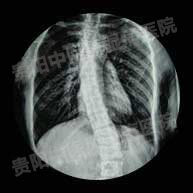

强直性脊柱炎临床诊疗

强直性脊柱炎图片对症分析2017-04-08